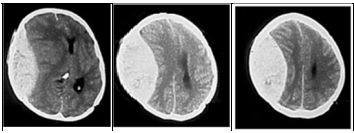

Um homem de 35 anos de idade foi vítima de acidente automobilístico e encaminhado ao pronto-socorro. Na admissão, estava consciente, comunicativo, com hálito etílico e com períodos confusionais e de agitação, mas movimentava todos os quatro membros sem deficits e deambulava. Não guardava nenhuma recordação do acidente (escala de coma de Glasgow = 14 pontos). Havia contusões no couro cabeludo e fratura da clavícula direita. Seis horas após a admissão, o paciente encontrava-se sonolento e respondendo mal aos comandos verbais (escala de coma de Glasgow = 11 pontos). As principais imagens do exame de tomografia computadorizada cranioencefálica (TC) sem contraste são mostradas abaixo.

Cortes axiais de TC de crânio sem contraste

Com base na história clínica, na evolução neurológica e no exame de neuroimagem desse caso hipotético, é correto afirmar que o diagnóstico é o de